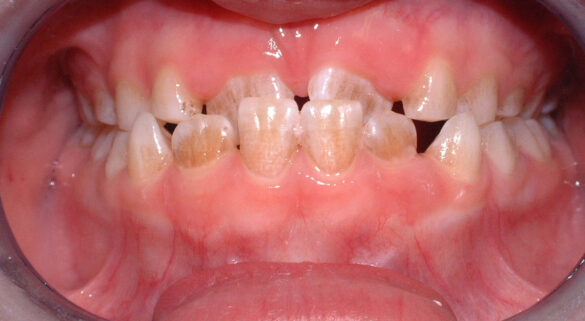

La momentul prezentării în clinică, în decembrie 2002, pacienta avea 8 ani şi o lună şi suferea de fibroză chistică şi de o deficienţă de dezvoltare a etajului mijlociu al feţei. Aceasta prezenta o anomalie de clasa I care mima o anomalie de clasa a III-a. Incisivii centrali, laterali şi caninii temporari maxilari, precum şi molarii prim şi secund de pe partea stângă erau în ocluzie inversă. În plus, pacienta prezenta coloraţii ale dinţilor de etiologie idiopatică (fig. 1). Autorii au considerat coloraţiile ca fiind de suprafaţă, extrinsece şi nu determinate de fibroza chistică, dovadă îndepărtarea acestora prin periaj profesional. Radiografia panoramică efectuată cu 6 luni înainte de prezentarea în clinica stomatologică relevă anodonţia incisivilor laterali superiori şi a premolarului secund drept inferior, ca şi posibila incluzie a caninilor maxilari, în special a celui stâng (fig. 2).